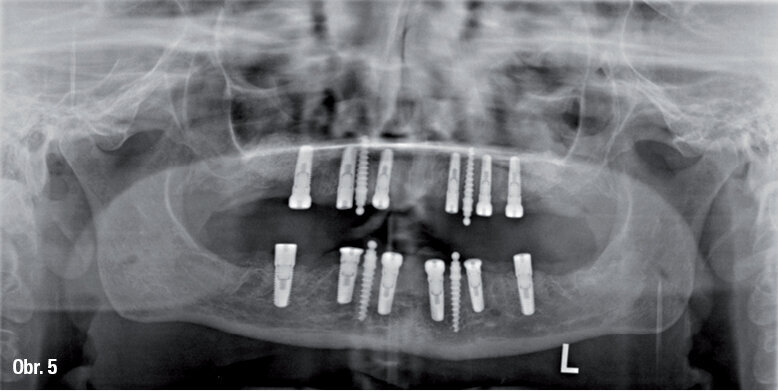

Po naplánování pomocí simulace na dentálním CT (příklad na obr. 4) a po odublování imediátní protézy jako operační šablony byly ve třetí a poslední fázi zavedeny implantáty do horní čelisti (obr. 5).

OPG snímek se 16 zavedenými implantáty a augmentovanými oblastmi